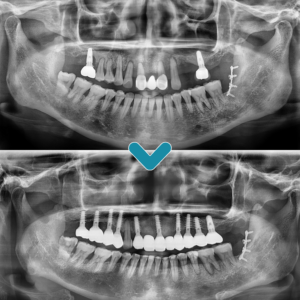

전주신시가지임플란트 꼼꼼하게 따져보고 결정해 주세요 . 임플란트는 상실된 치아를 대신하기 위해 인공적으로 만든 치아 뿌리를 턱뼈에 심어, 그 위에 보철물을 올려 자연치아와 유사한 기능을 회복시켜주는 치료법입니다. . 치아가 빠지면 저작 기능 저하, 발음 문제, 인접 치아의 이동 등 여러 가지 문제가 발생할 수 있습니다. . 임플란트는 이러한 문제를 해결하며 심미성까지 더보기…